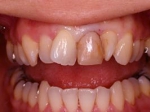

インセラム(オールセラミック)症例①

治療前治療前インセラム(オールセラミック)冠による修復。 主訴は前歯が汚い 金属を使わないオールセラミックでの治療を勧めた。 術前 治療後治療後術後

インセラム(オールセラミック)症例②

治療前治療前術前 治療後治療後術後 歯の尖端の透明感までよく再現できている。